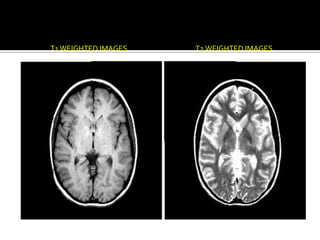

T1 WEIGHTED IMAGES   T2 WEIGHTED IMAGES

Principios básicos IRM

Permite detectar núcleos anormales

Permite el estudio de procesos metabólicos

φ       Núcleos se alinean en un fuerte campo magnético

φ       Se puede emitir un pulso de radiofrecuencia que provoca que el núcleo absorba y

emita energía.

φ       La lectura en IRM adquiere la forma de un espectro y se puede convertir en una

imagen cerebral.

…Contd T1 WEIGHTED IMAGES T2 WEIGHTED IMAGES